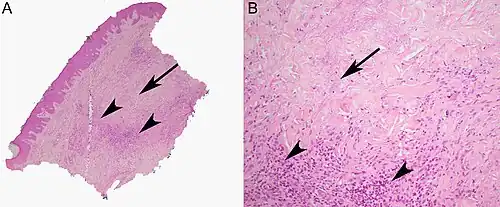

Histopathology

Although the exact cause of this condition is not known, it is an inflammatory disorder characterized by collagen degeneration, combined with a granulomatous response. It always involves the dermis diffusely, and sometimes also involves the deeper fat layer. Commonly, dermal blood vessels are thickened (Microangiopathy).[21]

Diagnosis

NL is diagnosed by a skin biopsy, demonstrating superficial and deep perivascular and interstitial mixed inflammatory cell infiltrate (including lymphocytes, plasma cells, mononucleated and multinucleated histocytes, and eosinophils) in the dermis and subcutis, as well as necrotising vasculitis with adjacent necrobiosis and necrosis of adnexal structures.[23] Areas of necrobiosis are often more extensive and less well defined than in granuloma annulare. The presence of lipid in necrobiotic areas may be demonstrated by Sudan stains. Cholesterol clefts, fibrin, and mucin may also be present in areas of necrobiosis. Depending on the severity of the necrobiosis, certain cell types may be more predominant. When a lesion is in its early stages, neutrophils may be present, whereas in later stages of development, lymphocytes and histiocytes may be predominant.[24]